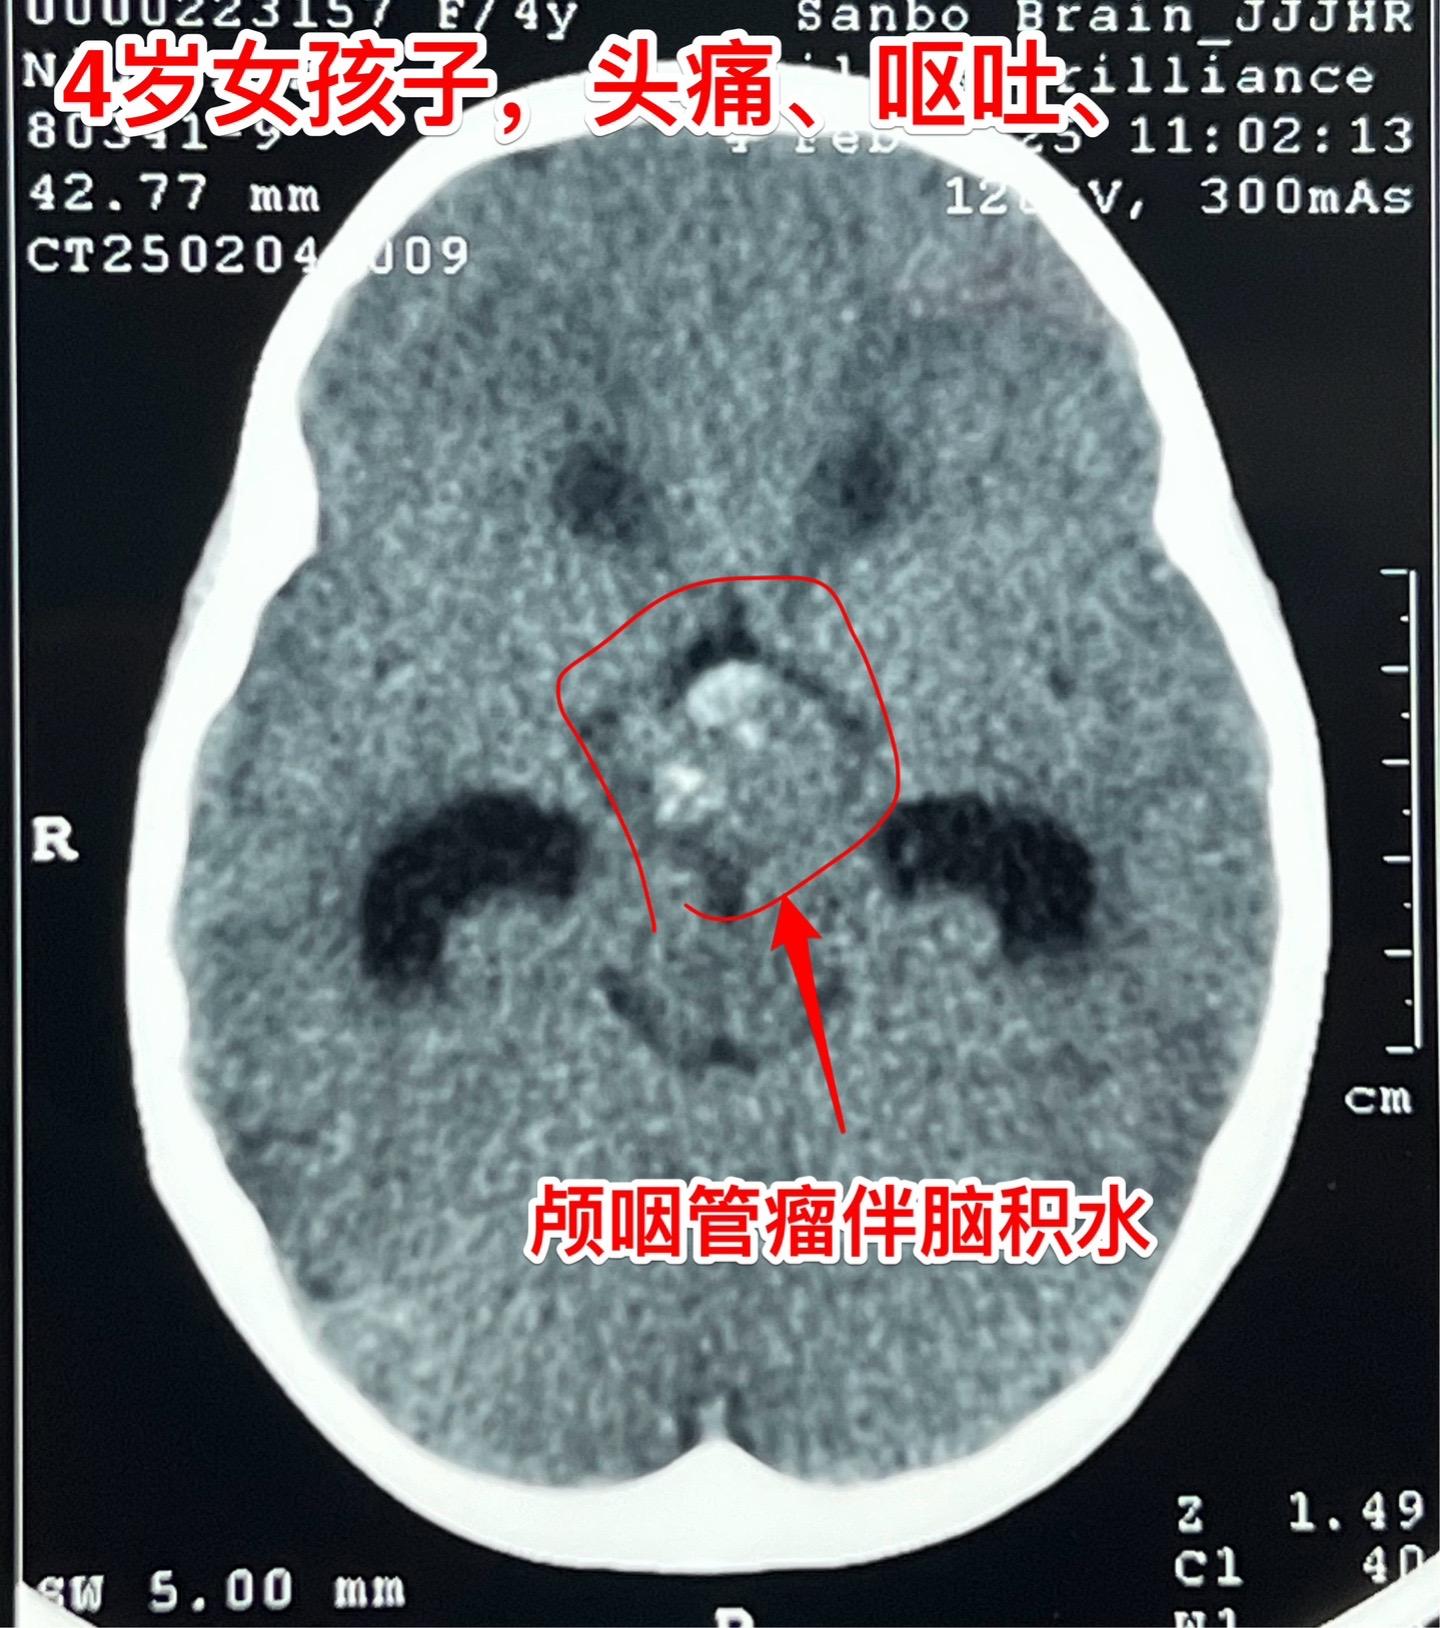

除夕当天发现颅咽管瘤,正月初七到三博住院。西安市的四岁女孩子,一个月前就开始出现头痛、间断出现呕吐,病情越来越严重,于1月28日就是除夕当天,在西安市行磁共振检查发现颅咽管瘤,伴有脑积水! 简直就是晴天霹雳! 在传统佳节里孩子的一家人处于诚惶诚恐之中。孩子头痛伴有呕吐,在当地医院每天都要输入甘露醇才能减轻症状。 正月初七一家人到三博脑科医院来住院。 正月初八正式上班,小孩子仍然有颅高压症状! 正月初九作了开颅手术,顺利切除